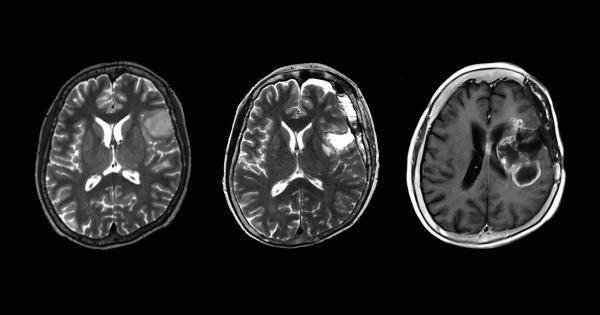

Екип от изследователи от Факултета по медицина към Университета в

...... диагноза на пациента с нискостепенен тумор вместо със злокачествен тумор; следователно нашите резултати предполагат, че лекарите трябва да обмислят възможността за такива тумори." Източник: Medical Xpress